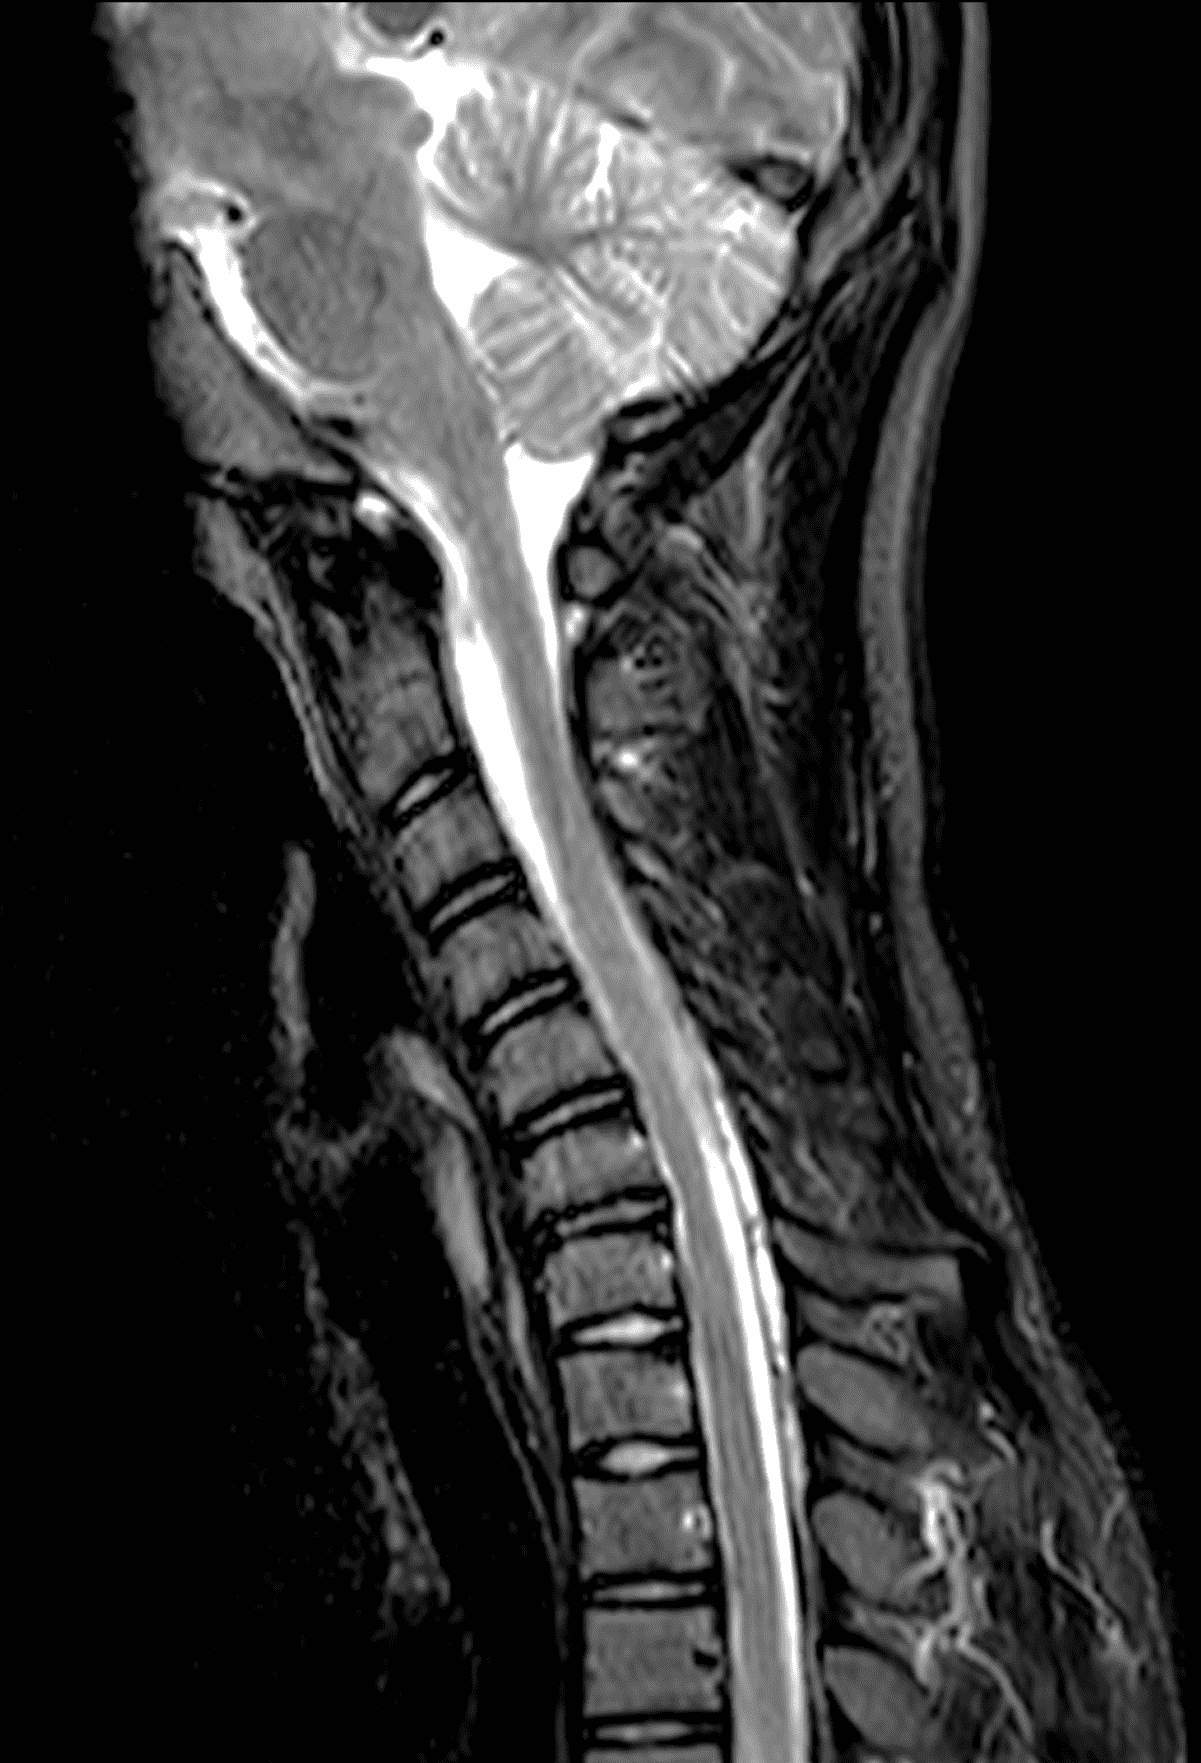

An 18 year old man presents with progressive motor wasting of right hand, progressive right hand weakness, claw-like deformity with flattening of the hand, and inability to straighten the ring and small fingers. He reports no numbness or pain. Sagittal T2-weighted (1A), sagittal T1-weighted (1B), sagittal STIR (1C), axial T2-weighted (1D), and axial T1-weighted (1E) images of the cervical spine obtained around the time of presentation are provided. What are the findings? What is your diagnosis?

Figure 2: Neutral images of the cervical spine. Sagittal (2A) T2-weighted, (2B) T1-weighted, and (2C) STIR images show mild kyphosis, an enlarged posterior epidural space with loss of attachment of the dura (red arrows), and cord atrophy at the C6 level (yellow arrow). Subtle cord hyperintensity on the water sensitive images at the C7 level (green arrows) likely represents gliosis. (2D) Axial T2-weighted image shows enlargement of the posterior epidural space, right greater than left (red arrows). (2E) Axial T1-weighted image shows an enlarged posterior epidural space (red arrows) and cord atrophy, more severe on the right (yellow arrow).